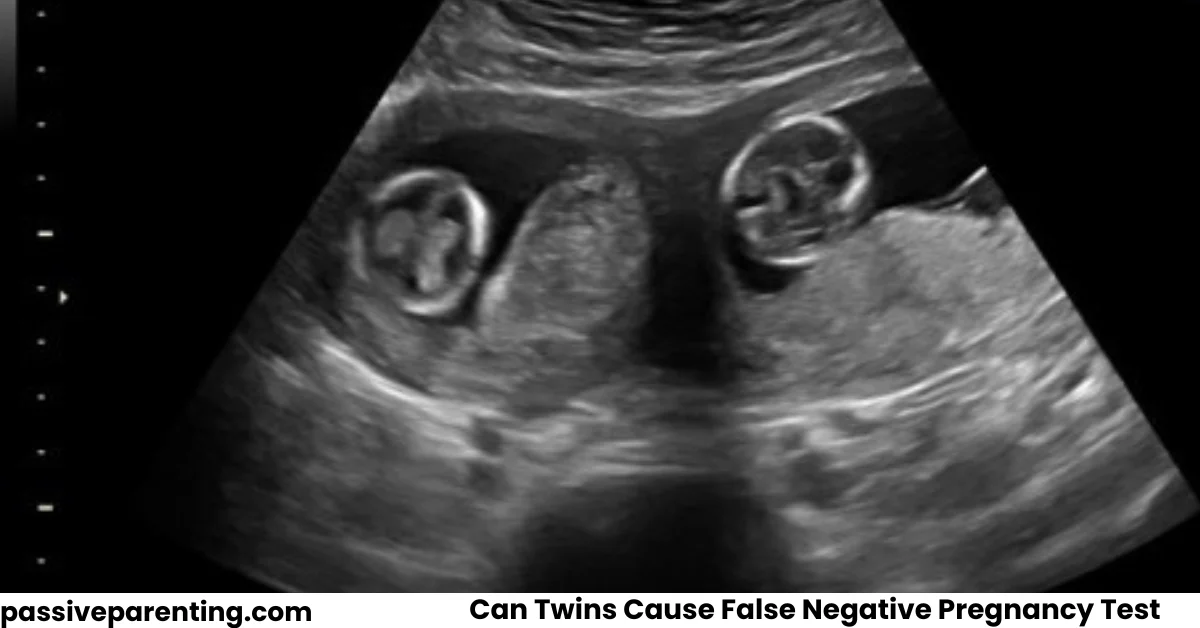

Ultrasound Imaging

Ultrasound is the most reliable way to confirm twins. It allows doctors to see the developing embryos directly.

Ultrasound is typically used to confirm multiple embryos.